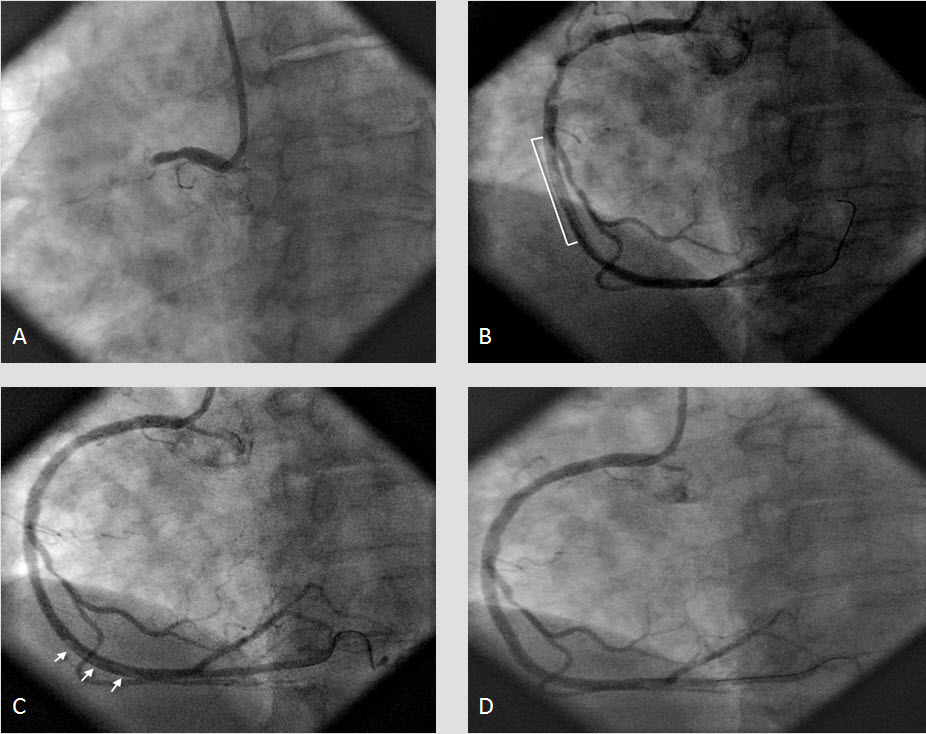

We present herein the case of a woman suffering from acute inferior myocardial infarction referred to our hospital for emergency catheterization after failed fibrinolysis and treated successfully with transradial rescue PCI. The case presentation is followed by a concise overview of data supporting the wider use of the radial approach, especially focusing on acute coronary syndromes.